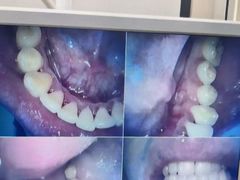

• 牙博士口腔品牌连锁(杨浦店)

• -牙博士口腔品牌连锁(杨浦店)